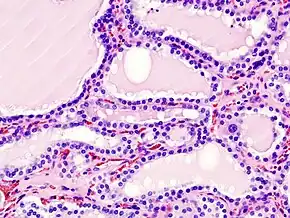

Graves' disease is an autoimmune disorder, in which the body produces antibodies to the receptor for thyroid-stimulating hormone. (Antibodies to thyroglobulin and to the thyroid hormones T3 and T4 may also be produced.)

These antibodies cause hyperthyroidism because they bind to the TSHr and chronically stimulate it. The TSHr is expressed on the thyroid follicular cells of the thyroid gland (the cells that produce thyroid hormone), and the result of chronic stimulation is an abnormally high production of T3 and T4. This, in turn, causes the clinical symptoms of hyperthyroidism, and the enlargement of the thyroid gland visible as goiter.

Biopsy to obtain histiological testing is not normally required, but may be obtained if thyroidectomy is performed.